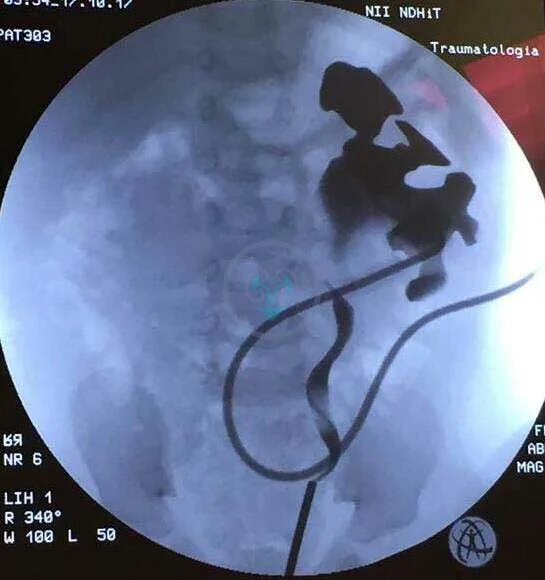

Гидронефроз почки после операции